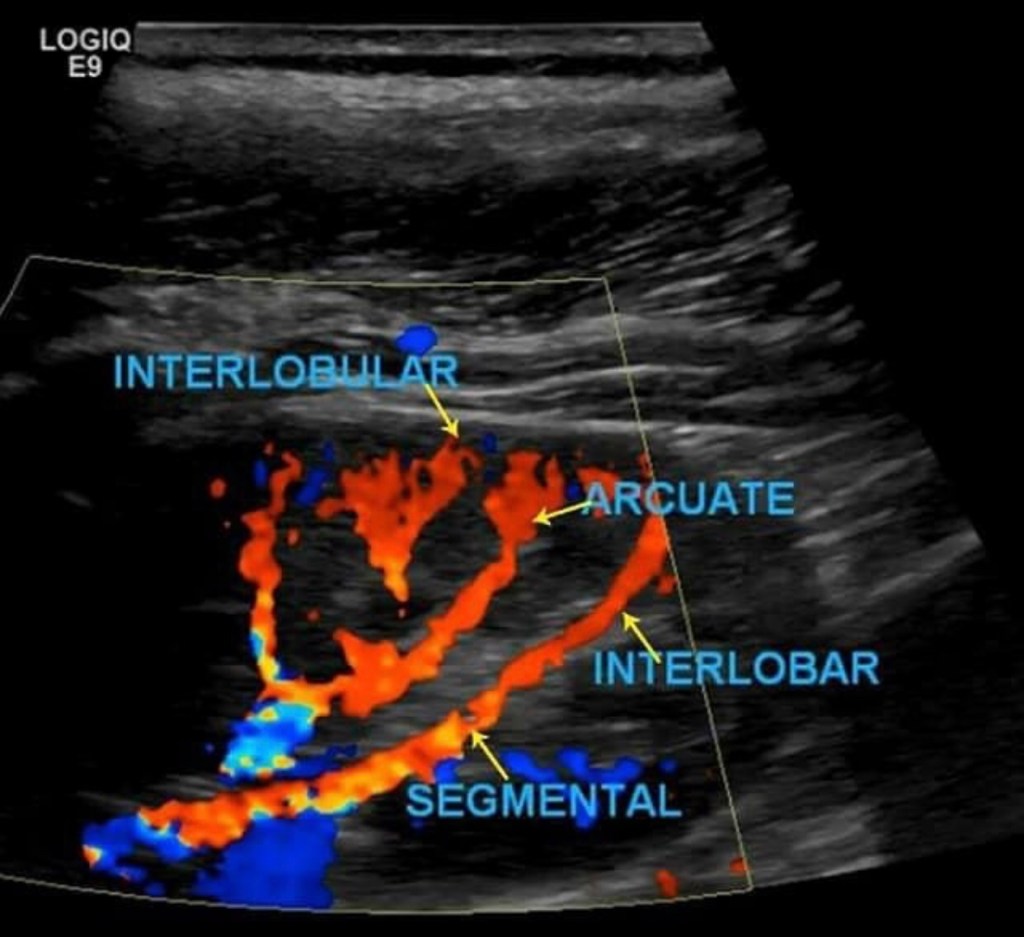

Once that is complete move on to Doppler the arcuate/segmental arteries (your institution may require one or the other or both). Doppler these arteries in the superior, mid and inferior pole of the kidney. Do not use angle correction.